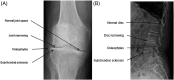

Intervertebral disc degeneration describes the vicious cycle of the deterioration of intervertebral discs and can eventually result in degenerative disc disease (DDD), which is accompanied by low-back pain, the musculoskeletal disorder with the largest socioeconomic impact world-wide. In more severe stages, intervertebral disc degeneration is accompanied by loss of joint space, subchondral sclerosis, and osteophytes, similar to osteoarthritis (OA) in the articular joint VSports手机版. Inspired by this resemblance, we investigated the analogy between human intervertebral discs and articular joints. Although embryonic origin and anatomy suggest substantial differences between the two types of joint, some features of cell physiology and extracellular matrix in the nucleus pulposus and articular cartilage share numerous parallels. Moreover, there are great similarities in the response to mechanical loading and the matrix-degrading factors involved in the cascade of degeneration in both tissues. This suggests that the local environment of the cell is more important to its behavior than embryonic origin. Nevertheless, OA is widely regarded as a true disease, while intervertebral disc degeneration is often regarded as a radiological finding and DDD is undervalued as a cause of chronic low-back pain by clinicians, patients and society. Emphasizing the similarities rather than the differences between the two diseases may create more awareness in the clinic, improve diagnostics in DDD, and provide cross-fertilization of clinicians and scientists involved in both intervertebral disc degeneration and OA. .